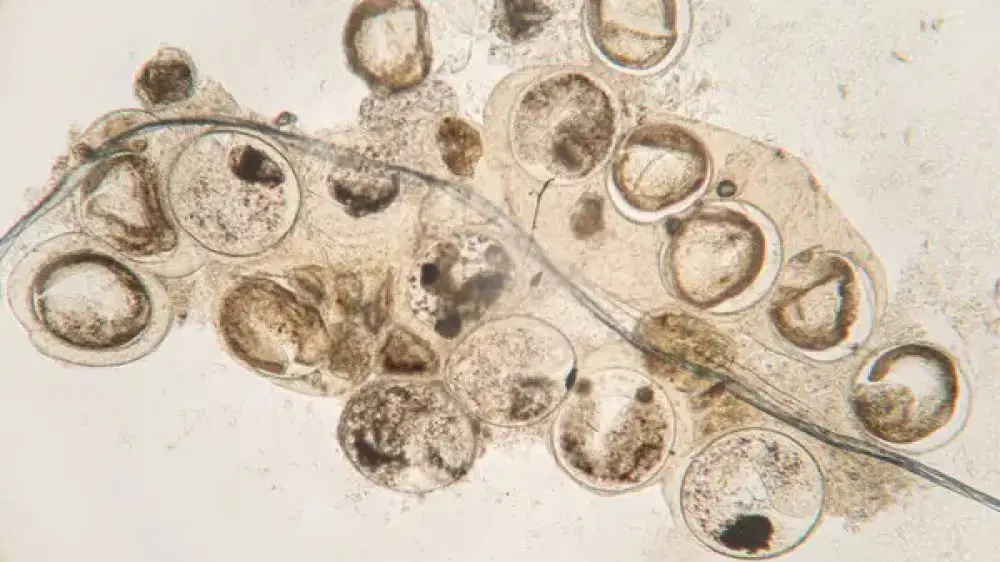

По словам инфекциониста Евгения Шаповалова, рыба нередко бывает заражена паразитами, многие из которых не видны невооруженным глазом. Стоит ли бояться есть рыбу или употребление морских обитателей не так страшно, как кажется, специалист рассказал в интервью порталу Doctorpiter, рассказывает Tengri Life.

Врач отмечает, что паразиты способны поражать как морскую, так и пресноводную рыбу.